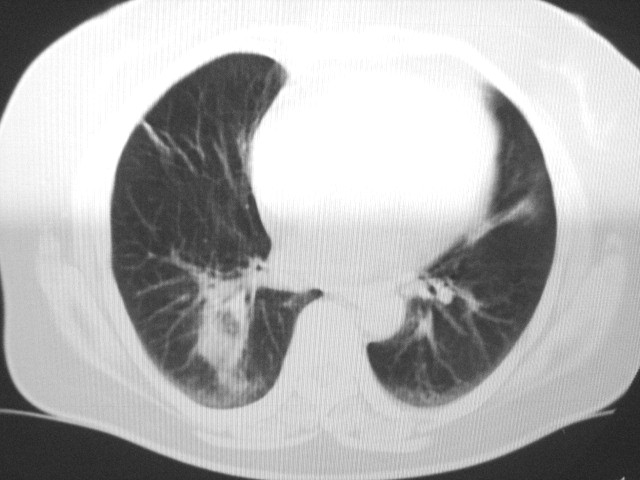

以下是引用清清楚楚在2007-8-28 7:13:00的发言:[br]右肺下叶可见斑片状高密度影,边缘模糊;右肺中叶内侧段及左肺舌段亦可见小斑片状模糊影。[br]考虑双肺感染,建议抗炎治疗后复查。

以下是引用天南地北在2007-8-27 23:49:00的发言:[br]右肺下叶可见斑片状高密度影,边缘模糊;右肺中叶内侧段及左肺舌段亦可见小斑片状模糊影。[br]考虑双肺感染,建议积极抗炎治疗后复查。

以下是引用天南地北在2007-8-27 23:49:00的发言:[br]右肺下叶可见斑片状高密度影,边缘模糊;右肺中叶内侧段及左肺舌段亦可见小斑片状模糊影。[br]考虑双肺感染,建议抗炎治疗后复查。

以下是引用难听在2007-8-28 13:17:00的发言:[br]右肺下叶背段支气管狭窄,是否可以考虑新生物伴阻塞性肺炎.请大家帮帮忙,这个病人是卫生局长的丈母娘.惹不起啊.